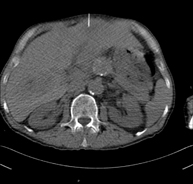

- CT-guided abdominal FNA (fine needle aspiration)

It consists in obtaining a tissue sample from a specific lesion located in the abdominal cavity. This test is performed using local anaesthesia on the puncture area, which is administered with fine-gauge needles. The entire procedure is monitored using images obtained by computed tomography (CT) at various stages of the puncture, using fluoroscopy-CT equipment. After the test, the patient remains under observation in hospital for a few hours. Coagulation tests must be performed before the puncture.

- CT-guided abdominal biopsy

It consists in obtaining a tissue sample from a specific lesion located in the abdominal cavity. It is sometimes performed under sedation with the help of an anaesthesia team. Needles are used to draw a cylinder sample from the lesion to be studied, which is then sent to the Pathology Department for histological analysis. The entire procedure is monitored using images obtained by computed tomography (CT) at various stages of the biopsy, using CT fluoroscopy. After the test, the patient remains in hospital under observation. Coagulation tests must be performed before the puncture.